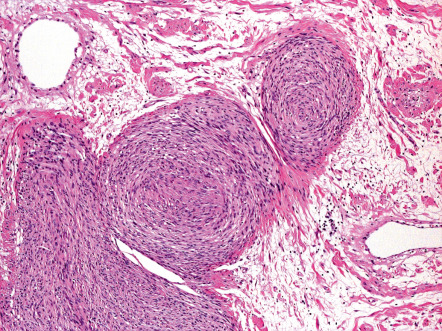

Neurofibromas are poor- to well-circumscribed, usually non-encapsulated, nodular or oblong tumors that can be located anywhere within the dermis and subcutis . The common solitary variant is usually present in the superficial dermis, creating a dome-shaped or polypoid elevation of its surface. The tumor is composed of a fine fibrillary lattice of haphazardly arranged slender spindle cells ( Fig. 115.9 ). The stroma can be variably vascular, fibrotic, edematous or myxomatous. In addition to Schwann cells and perineurial cells, plump fibroblasts and mast cells are present. Palisading of nuclei can occur, but true Verocay body formation is rare . Mitotic figures are absent or rare. The diffuse form has an essentially similar cytology, but lacks a well-defined growth pattern as it infiltrates adjacent structures. Atypical forms of neurofibromas have been described .

As opposed to superficial, solitary and diffuse forms, neurofibromas which are seated within the lower reticular dermis, subcutis, and other deep soft tissues are usually encapsulated by perineurium or epineurium and may show a plexiform growth pattern ( Fig. 115.10 ) ; the latter is defined as irregularly expanded, twisted, and interconnected nerve fascicles arranged in lobular structures. Variants with a combined diffuse and plexiform growth pattern usually occur in NF1. By utilizing special stains, rare scattered axons can be demonstrated in both the superficial and deep variants of neurofibroma.